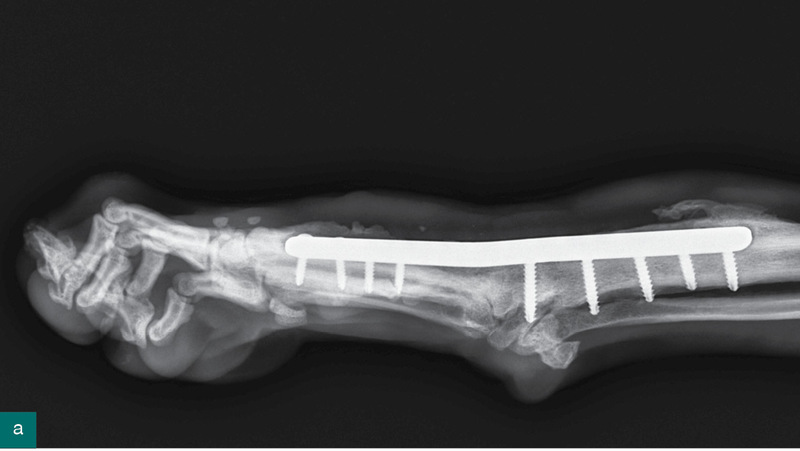

Ryc. 5. Stan zrostu kości trzy miesiące od wykonanego zabiegu artrodezy stawu nadgarstka.

W opisywanym przypadku zdecydowano o artrodezie wszystkich stawów nadgarstka (pankarpalnej), która jest wskazana, gdy zmiany dotyczą stawu przedramienno-nadgarstkowego, stawu śródnadgarstkowego lub nadgarstkowo-śródręcznego, gdy następuje uszkodzenie więzadeł dodatkowych nadgarstka, chrząstki włóknistej dłoniowej i więzadeł dłoniowych. Jeżeli staw przedramienno-nadgarstkowy nie jest uszkodzony, a zmiany dotyczą pozostałych struktur, bez przemieszczenia kości dodatkowej nadgarstka lub kości łokciowej nadgarstka, wystarczająca może być częściowa artrodeza nadgarstka (6, 7). Opisano trzy techniki całkowitej artrodezy nadgarstka: dłoniową, grzbietową, przyśrodkową. Idealny kąt dla pankarpalnej artrodezy to 10-12 stopni przeprostu. Podczas usuwania chrząstki stawowej należy zwrócić uwagę, aby usunąć ją do poziomu kości podchrzęstnej, nie pozostawiając dużych szczelin między powierzchniami stawowymi. Umieszczając przeszczepianą tkankę kostną między powierzchniami stawowymi, należy zachować jak najkrótszy czas odsłonięcia materiału przeszczepianego (3, 8). Ważne jest, aby jedna ze śrub znajdowała się centralnie w kości promieniowej nadgarstka. Można użyć igieł iniekcyjnych, aby umieścić płytę precyzyjnie, w odpowiednim miejscu.

Opisane powikłania przy zabiegu artrodezy obejmują poluzowanie śrub, złamanie zrostu kostnego, zakażenie, złamanie kości śródręcza, niepełną artrodezę i ciągłe zaburzenia chodu. Aby zmniejszyć ryzyko powikłań, należy zwracać uwagę, by nie uszkodzić ważnych anatomicznie struktur, usunąć całą chrząstkę ze wszystkich powierzchni, w odpowiedni sposób dogiąć płytę, tak aby nie było zbyt dużego, ale też zbyt małego kąta przeprostu. Trzeba również uważnie dobrać rozmiar płyty, by obejmowała ponad 50% długości kości śródręcza III (9). Wkręty należy umieszczać tak, aby śruby w kości śródręcza nie przekraczały 40% średnicy kości (10).

Ważne są też zalecenia pooperacyjne, między innymi ograniczenie ruchu, antybiotykoterapia, regularne zmiany opatrunku, zabezpieczenie rany przed wylizaniem poprzez używanie kołnierza. W jednej publikacji badano na grupie 17 psów czas gojenia się bez powikłań artrodezy pankarpalnej (12). U wszystkich pacjentów położono płytę dogrzbietowo oraz po zabiegu założono opatrunek gipsowy na sześć tygodni, a następnie opatrunek Roberta Jonesa na osiem tygodni, przy czym przez cały czas ograniczano ruch. W stawach międzynadgarstkowym i nadgarstkowo-śródręcznym zrost kostny nastąpił między 9. a 12. tygodniem, a w stawie promieniowo-nadgarstkowym między 17. a 30. tygodniem po operacji. Autorzy badania doszli do wniosku, że ocenę radiograficzną należy wykonać po sześciu i 12 tygodniach od zabiegu (12).